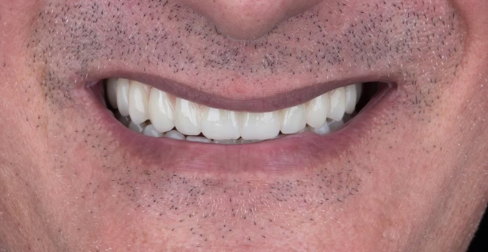

Some of Our Cases